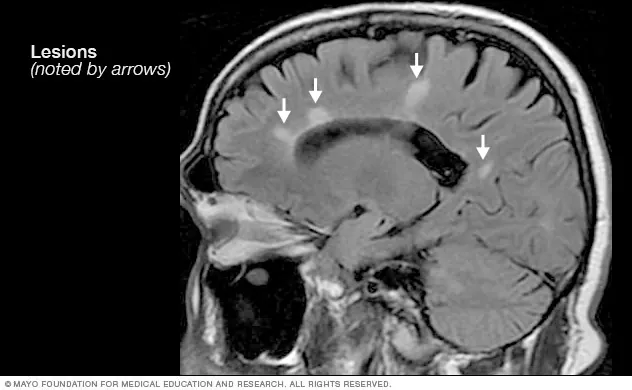

مسح رنين مغناطيسي لدماغ يظهر آفات بيضاء مرتبطة بالتصلب اللويحي (Mayo Clinic) فضلاً عن ذلك، فإنّ دراسات وجدت أن العلاجات التدخلية والميكانيكية للأوردة والانضغاطات النخاعية وتوترات العضلات والفقرات، غير مجدية، بل غير موصى بها، مثل دراسة نشرتها الأكاديمية الأميركية لعلم الأعصاب AAN) في أيلول/ سبتمبر 2018، التي خلصت نتائجها إلى أنه لا يُنصح بإجراء جراحات توسيعية للوريد الوداجي، بغرض تحسين أعراض مرض التصلب اللويحي. وكان العامري قد روّج أيضاً لعلاج التصلب اللويحي بلسعات النحل الحي في اللقاء نفسه، وكذلك عبر حسابه على منصة إكس، وهو ادعاء يناقض المصادر العلمية الموثّقة، مثل الدراسة التي نشرتها الأكاديمية الأميركية لعلم الأعصاب في 2005، وخلصت إلى أن استخدام لسعات النحل لم يُؤدِّ إلى تقليل نشاط التصلب اللويحي عند المصابين به، بل لم يُؤدِّ إلى تحسين الحياة لديهم. ورغم أنّ دراسة أخرى أحدث نُشرت في مجلة Neuropeptides المحكمة في تشرين الأول/ أكتوبر 2024، وصفت سمّ النحل بالعلاج الواعد لأمراض الجهاز العصبي المركزي، إلا أنّها توصلت أيضاً إلى أن لسعات النحل الحي تُشكّل خطراً أكبر متمثلاً في حدوث ردات فعل تحسسية شديدة. وبصورة عامة، لم تخلص هذه الدراسة أو غيرها إلى نتيجة نهائية بإمكانية استخدام لسعات النحل لعلاج التصلب اللويحي بشكل مباشر.